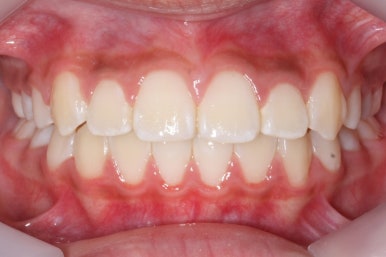

초진 시의 모습입니다.

11살의 어린이였기에 몇 군데 아직 유치가 남아있었습니다. 영구치가 모두 나오지 않았죠. 덧니가 있고 치열이 고르지 못하더라도 일반적으로 영구치가 더 나온 후에 연산동덧니교정 하는 것을 권해드립니다.

연산동덧니교정을 하고자 키다리아저씨치과에 처음 내원했을 때와 개선이 된 후의 비교 모습입니다. 영구치가 모두 나왔고 덧니가 개선이 된 후에 마무리가 되었습니다.